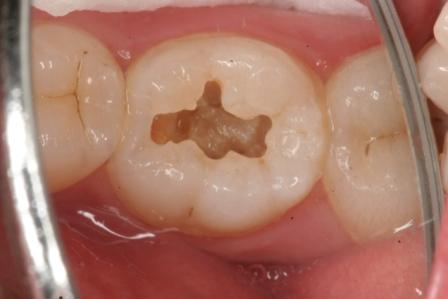

下顎7番の頬側歯茎部カリエスの原因 2025.06.04